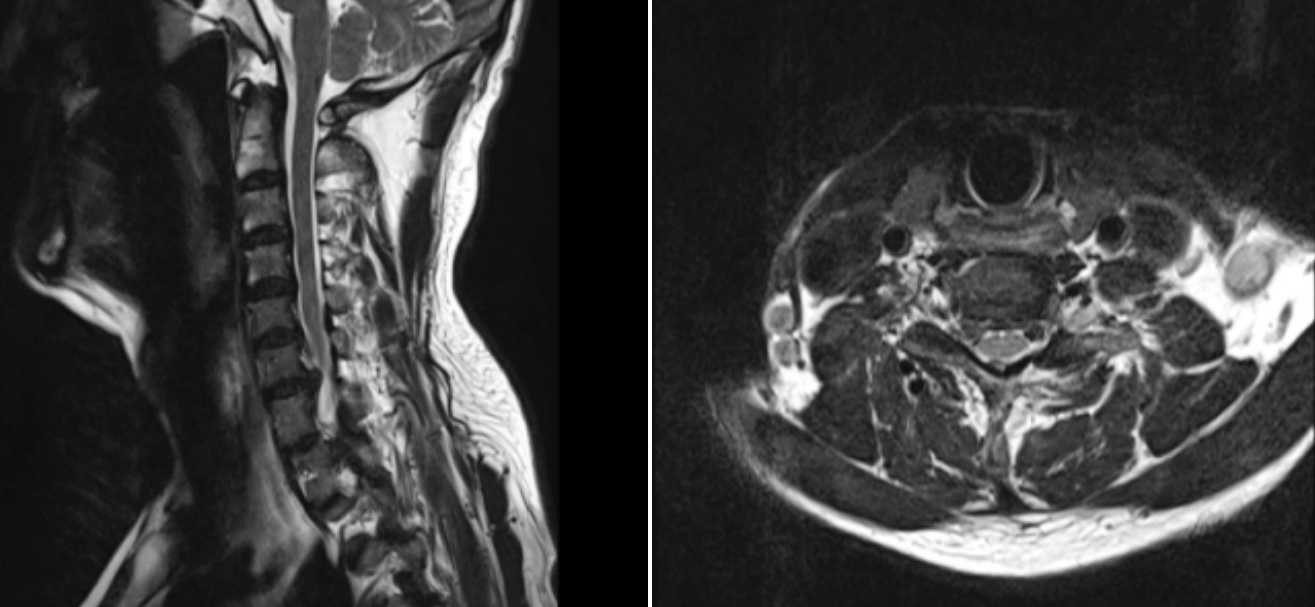

術(shù)前MRI圖像

患者,男,65歲,近期飽受右側(cè)上肢疼痛與麻木之苦,歷時三周之久。在外院嘗試保守治療措施,效果不佳,來我院就診。經(jīng)過醫(yī)療團(tuán)隊周密而細(xì)致的檢查,患者被明確診斷為“神經(jīng)根型頸椎病”,精準(zhǔn)地指出了其癥狀的根本原因。